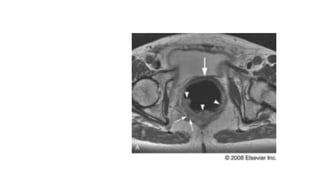

Imagen por Resonancia Magnetica

• Para valorar con mayor precision la recurrencia de cancer de recto

• Determina si existe extension del tumor en el suelo de la pelvis

Imagen por ResonanciaMagnetica • Para valorar con mayor precision la recurrencia de cancer de recto • Determina si existe extension del tumor en el suelo de la pelvis